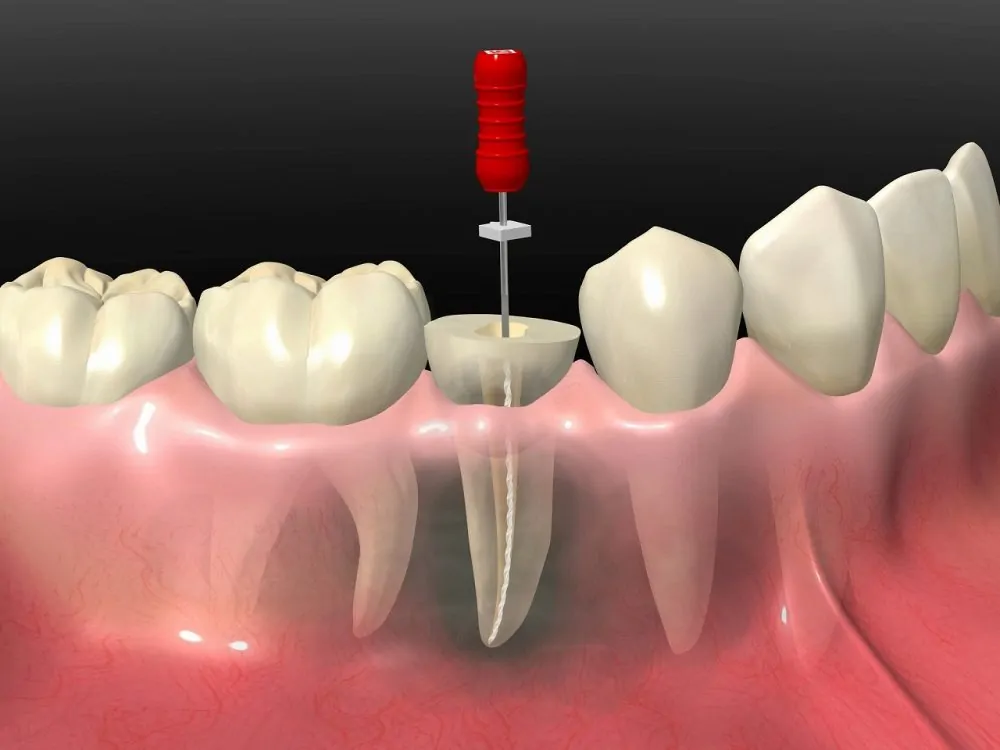

歯を守るための根管治療

重度のむし歯に対し、歯をできるだけ残すための根管治療を行っています

重度のむし歯に対し、歯をできるだけ残すための根管治療を行っています

みつい歯科クリニックでは、重度のむし歯に対し、歯をできるだけ残すための根管治療を行っています。むし歯が進行し、歯の神経にまで達した場合でも、根管治療を通じて抜歯を避けられる可能性があります。この治療は、歯の内部を丁寧に洗浄し、細菌を徹底的に除去したうえで薬剤を詰め、歯を保存する重要な方法です。

根管治療は、非常に精密な技術が求められる治療です。みつい歯科クリニックでは、拡大鏡を活用することで肉眼では見えにくい細部まで確認しながら作業を進めています。これにより、感染源を確実に除去し、再治療のリスクを減らすことが可能になります。

治療の際には、患者様の症状や進行状況に合わせた丁寧な説明を心がけ、納得していただいたうえで治療を進めます。治療後も経過観察を行い、歯が長持ちするようにサポートしています。みつい歯科クリニックでは、患者様に安心して治療を受けていただける環境と技術を提供しています。

根管治療は、非常に精密な技術が求められる治療です。みつい歯科クリニックでは、拡大鏡を活用することで肉眼では見えにくい細部まで確認しながら作業を進めています。これにより、感染源を確実に除去し、再治療のリスクを減らすことが可能になります。

治療の際には、患者様の症状や進行状況に合わせた丁寧な説明を心がけ、納得していただいたうえで治療を進めます。治療後も経過観察を行い、歯が長持ちするようにサポートしています。みつい歯科クリニックでは、患者様に安心して治療を受けていただける環境と技術を提供しています。